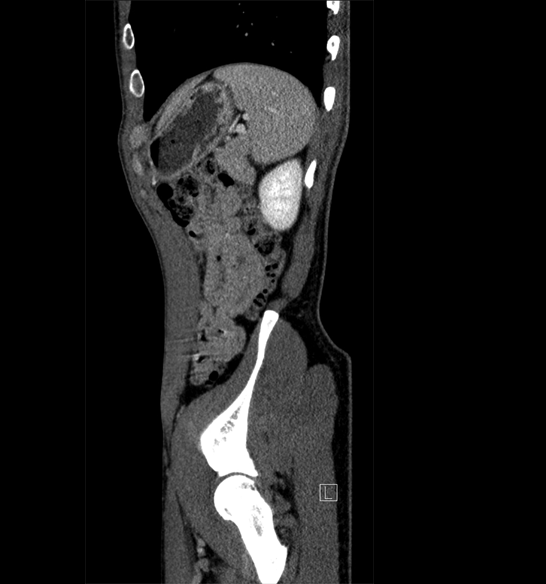

Body

Covers abdominal CT anatomy.